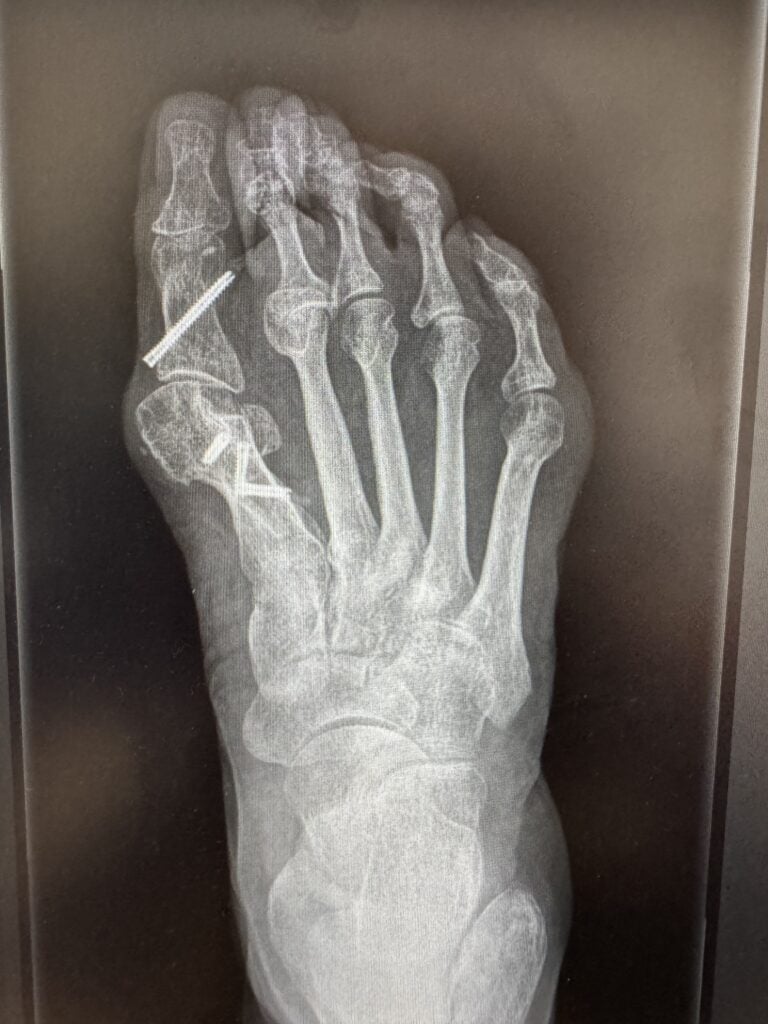

• Przezskórna operacja stopy często umożliwia zaradzić nawet znacznym deformacjom w małoinwazyjny i skuteczny sposób. Dotyczy to także sytuacji gdy mamy nawrót koślawości palucha po innej operacji. Ze względu na trudną technikę zabiegową i nierzadko obecne śruby po poprzednim zabiegu, konieczna jest wnikliwa kwalifikacja oraz dokładne badania obrazowe.